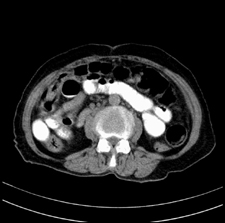

患者,女,75岁。腹痛,体黄5日,膝胸位时腹痛缓解。肝功能明日出来。彩超提示胆总管占位,未见血流信号。心电图提示s-t段改变。患者体质较弱,未能增强。

胆总管多发结石伴肝内外胆管轻度扩张。

胆总管多发结石伴肝内外胆管扩张。

胆管没有鼠尾征,还是考虑结石

胆管结石并发胆管炎。